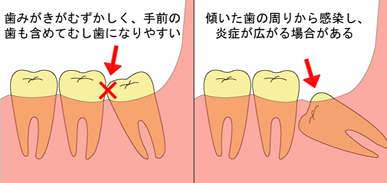

「親知らず」ってどういうときに抜くの |

|

| 次回の口腔外科のオペの日は |

|

|

ゴールデンウイークの関係上、 5月16日(金曜日)を予定しております |

![]() 親知らずの抜歯などの口腔外科

親知らずの抜歯などの口腔外科